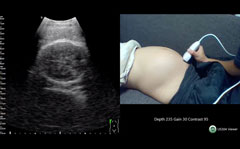

画像評価ー超音波所見② * 2.Placentalacuna $ * (胎盤中の血液間隙)$ ※Lacuna:空隙、小穴の意味$ * 1992年 最も有用な癒着胎盤 の超音波所見として初めて報(図D69)1) 全前置胎盤(33W)の超音波断層像 経腹走査法 経膣走査法 (図D69)2) 全前置胎盤の経膣超音波像 ・上段:前壁付着(31W) 性器出血あり内子宮口付近 の低エコー域は血液貯留を 示す所見 ・下段:後壁付着(30W) spongelike echoまたは胎盤絨毛血管腫は絨毛膜の絨毛血管から発生する良性nontrophoblastic tumorである。発生頻度は詳細に胎盤を調べると約1%(Fox)から014% 2) )ぐらいと考えられるが,鶏卵大以上の血管腫は極めてまれである。 一方,その臨床的意義に関しては,大部分は無症状であるが,大きさや臍帯付着部と

前置胎盤や前置癒着胎盤の帝王切開は産科医 にとって最もストレスを感じる手術の一つと言える. 前置胎盤の発症率は1000出生に対し5~139と 諸外国に比較して日本人では比較的高い. 近年では帝王切開率の上昇もあり前置癒着胎盤好な画像を描出できる。また胸腺が発達してい るため胸骨上部周囲からもエコーが良好に入る ことが多い。 「水平断面連続スキャン法」では、プローブの操 作に特別なトレーニングは必要ないが、画像診断 には知識と経験の蓄積が必要である。習熟すれば3)胎盤 位置(低い場合は後ほど経腟超音波) 異常の有無(肥厚、血腫、腫瘍など) 4)臍帯 2a1vか? 画像 の2つの見方 (06年 胎児心エコー

妊娠経過と胎盤超音波像 超音波断層像で胎盤を観察していると,とくに妊娠末期に至って画像上の変化の生ずるものがあることが1973年にWinsberg 1) によって最初に報告された。 続いてFisherら 2) は胎盤像が妊娠初期から末期まで,継続的に変化するとし,とくに最後の3〜4週間に石灰化による

25 胎盤 臍帯の超音波像 日本産婦人科医会